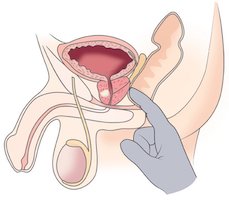

Wir biopsieren immer mithilfe von Live-Bildern des MRT während der Untersuchung. Nur so erreichen wir eine Trefferquote von über 99 Prozent von verdächtigen Befunden. Durch die Kombinationsbiopsie der ALTA Klinik kann der Patient eine maximale Sicherheit bekommen, weil gezielt verdächtige Stellen biopsiert werden können und zusätzlich systematische Proben aus der Prostata entnommen werden.

Die Grundlage für eine Abklärung ist die multiparametrische MRT-Untersuchung der Prostata. Mit hochauflösenden Schnittbildern können wir Erkrankungen bereits im Frühstadium feststellen. Dabei kontrollieren wir die gesamte Prostata in Dünnschichtaufnahmen. Zu unterscheiden sind gutartige, entzündliche oder bösartige Erkrankungen. Bei einem Mann können auch mehrere Erkrankungen gleichzeitig auftreten. Es kommt vor, dass Männer eine gutartige, altersbedingte Vergrößerung der Prostata, einen chronischen Entzündungsherd und zusätzlich noch einen bösartigen Tumor in der Prostata haben. Unsere MRT-Untersuchung kann all diese Erkrankungen aufdecken. Für uns gehört neben der aussagefähigen MRT-Untersuchung der Prostata auch die Einbeziehung von Laborwerten, wie Analyse von PSA-Werten, PSA-Verlauf und Bewertung von Entzündungsparametern usw. dazu. Die Laborwerte können insbesondere bei Grenzfällen helfen oder eine Bestätigung für eine festgestellte Diagnose sein.

Wir biopsieren immer mithilfe von Live-Bildern des MRT während der Untersuchung. Nur so erreichen wir eine Trefferquote von über 99 Prozent von verdächtigen Befunden.